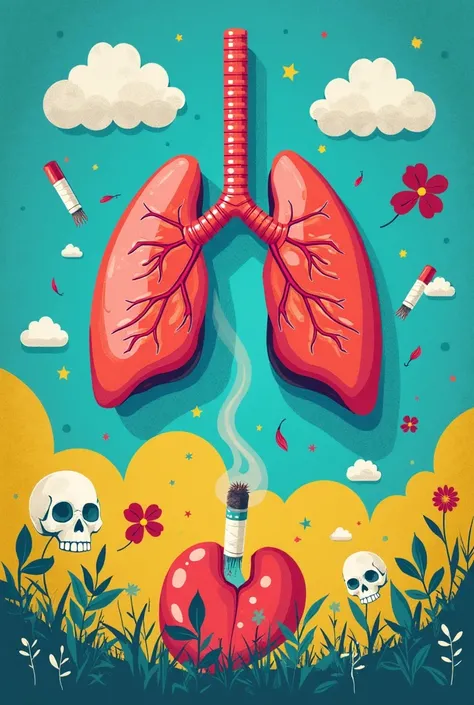

Generate a lungs, the right side lungs is healthy vibrant color surrounded with

Generate a lungs, the right side lungs is healthy vibrant color surrounded with fresh air. On the left side make the lungs damage or pollution of elements in smoking. Add some symbols of no smoking in the pulution part, and add some clean air in the right side lungs

the right side lungs is healthy vibrant color surrounded with fresh air

Add some symbols of no smoking in the pulution part

and add some clean air in the right side lungs